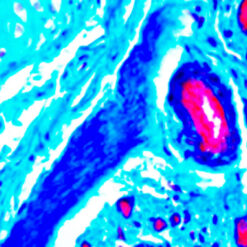

Lambda Light Chain-FITC

Traces of contaminating antibodies have been removed by solid phase absorption. Only the lambda precipitation line appeared in cross immunoelectrophoresis. This antibody is well suited for tissue section staining but may also be used for other applications.

| Description/Type | FITC Conjugated Antibody |